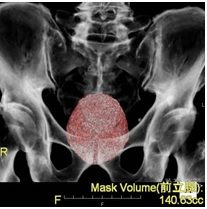

PSAが高値などの前立腺がんを疑う場合は、前立腺のMRI検査を行います。 前立腺MRIは、前立腺がんの診断に大変有用な検査で、前立腺がんの有無だけではなくがんの位置や大きさ、悪性度もある程度予測する事が可能となります。 また、疑わしい場所があった場合に行う前立腺生検の際、こちらの画像を前立腺生検の装置に取り込み、実際の超音波画像と融合する事により正確に前立腺がんと疑われる場所の組織を採取する事が出来ます。(MRI融合前立腺生検)